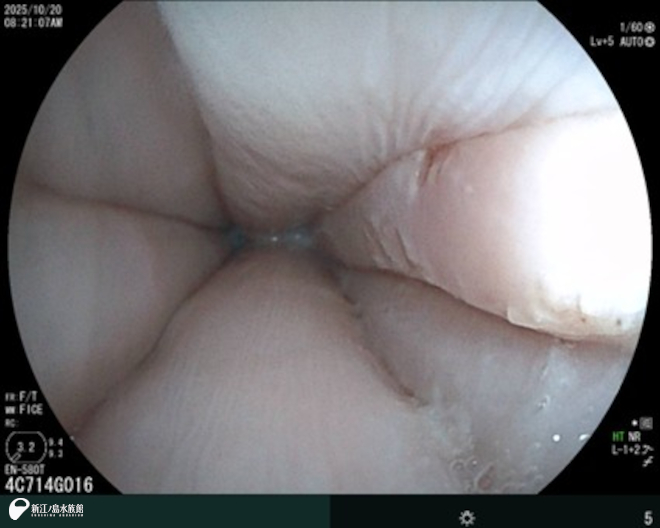

次は、内視鏡。

先端に超小型のカメラを搭載した細長い管を体内に挿入し、消化管や気管支など内部をリアルタイムの映像で観察、診断、治療することができます。胃潰瘍や異物誤飲の確認や除去、人工授精などで使用します。こちらも 2台の機械を持っていて、動物種や状態に合わせて使用しています。

2025年 バンドウイルカ「ニコ」の食道。

2024年 アオウミガメ「ティダ」の食道のようすです。ウミガメ類は口から食道にかけて、後ろ向きにとげとげした突起がたくさん並んでいます。捕獲した獲物の逆流を防ぐ役割を果たしているといわれています。ウミガメの食道はとげとげしていると聞いたことはありましたが、初めて自分の目で見た時は本当にとげとげしているんだ!と思ったことを今でも鮮明に覚えています。